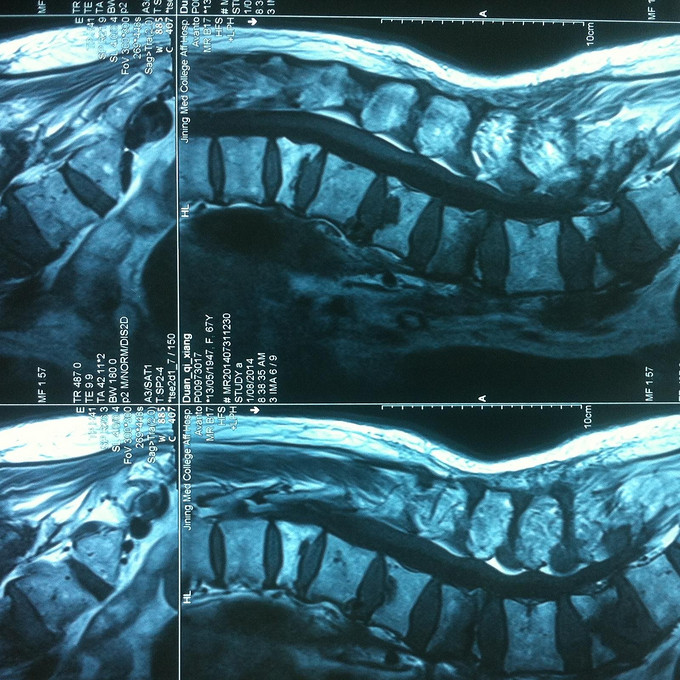

查体:腰部活动受限,腰骶部叩痛明显,体位试验阳性,双下肢感觉无减退,双侧屈髋、伸膝、踝背伸、踇背伸、跖屈肌肌力4-5级,双侧膝腱反射++,跟腱反射+,双侧巴氏征阴性。 辅助检查: X-ray:骨质疏松,腰3、5楔形变,MR:骨质疏松,腰3、5新鲜骨折

诊断:腰椎骨折 骨质疏松症 处理: 1、完善相关辅助检查,明确诊断,有无手术指证; 2、完善手术评估,有无手术禁忌,手术风险及并发症; 3、在局麻下行腰椎骨折椎体pkp术 4、术后给予全身抗骨质疏松治疗